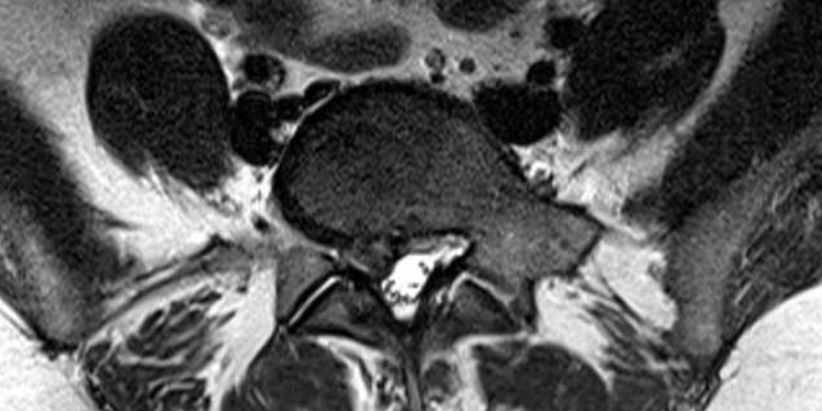

Ελάχιστα Επεμβατική Δισκεκτομή Ο4/5 δεξιά